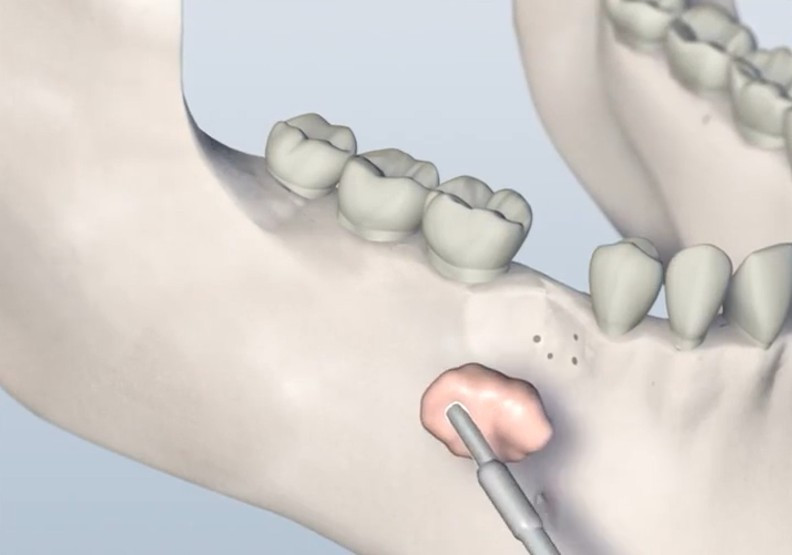

Minor grafting procedures are often performed in preparation for dental implants, especially when the bone is too thin or soft to support an implant securely. These procedures are typically done in-office under local anesthesia or IV sedation.

• Socket preservation (graft placed immediately after a tooth extraction)

• Ridge augmentation (to rebuild natural contours of the jawbone)

• Guided bone regeneration (GBR) using specialized membranes to support healing and bone regrowth

These techniques improve bone volume and quality, creating the ideal conditions for successful implant placement.